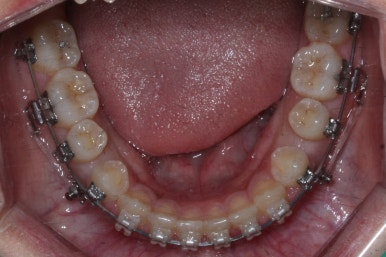

서서히 틈이 줄어들고 있는 것이 보입니다.

벌써 몇 군데는 틈이 다 모였습니다.

이제 거의 다 끝나가고 조금 더 마무리하면 됩니다.

부산치아교정치과에서 치료한 이 사이가 벌어진 틈새교정을 마무리 했을 때의 모습을 보여드리겠습니다.

몰라보게 바뀌었습니다.

틈새가 다 모였고 다시 틈이 벌어지지 말라고 앞니 안쪽에는 유지장치를 달고 마무리를 했습니다.